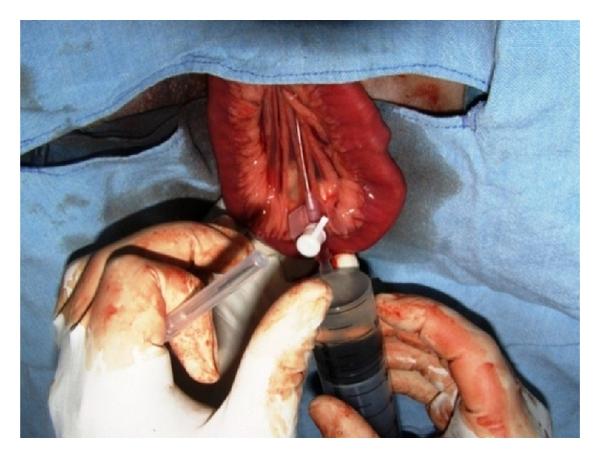

Hepatic disease is often treatable and has a predictable prognosis when a definitive diagnosis is made. The aim of clinicopathological evaluation of hepatobiliary affections is to identify and characterize hepatic damage and dysfunction, identify possible primary causes of secondary liver disease, differentiate causes of icterus, evaluate potential anaesthetic risks, assess prognosis and response to xenobiotics, and monitor response to therapy. This paper describes the different diagnostic methods and imaging techniques employed in diagnosis of hepatobiliary affections in dogs. Besides reviewing the significant clinical manifestations and imaging structural abnormalities in diagnostic approach to different hepatic affections, it also depicts radiographic, ultrasonographic, and wherever applicable, the laparoscopic characterization of different hepatic affections and target lesions encountered in clinical cases presented in the Teaching Veterinary Clinical Complex, COVAS, Palampur in the year 2007-2008.

肝病通常是可治疗的,一旦做出明确诊断,其预后是可预测的。肝胆疾病临床病理评估的目的是识别和描述肝损伤及功能障碍,确定继发性肝病可能的主要病因,鉴别黄疸的病因,评估潜在的麻醉风险,评估预后及对外源化学物质的反应,并监测治疗反应。本文描述了用于诊断犬肝胆疾病的不同诊断方法和成像技术。除了回顾不同肝病诊断方法中的重要临床表现和成像结构异常外,还描述了2007 - 2008年在帕兰普尔兽医临床综合教学中心(COVAS)出现的临床病例中不同肝病及目标病变的放射学、超声学特征,以及在适用情况下的腹腔镜特征。